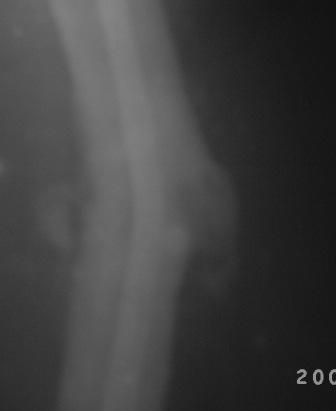

12.02.09г б-ная оперирована: з/остеоклазия (без особого труда- видимо тугой ложный сустав) коррекция деформации, удаление штифта из надвертельной обл, рассверливание канала гибкими развертками, реостеосинтез блокируюшим гвоздем Д-11мм.

Но я впервые почувствовал такую сильно ОСТЕОПОРОТИЧНУЮ кость, что блокируюшие винты проваливаются внутрь кости, что винты можно ввести без сверления кости, и что винты провинчиваются холостую, т.е. не стабильно.

P.S. Снимки не качественные, извиняюсь! последний снимок ЭРГА, два снимка объединил.

Я заранее приношу свои извинения, но по демонстрации видно, что сама методика БИОС использована с нарушениями. Да я с Вами согласен и сам часто встречался подобными случаями, когда из-за отсутствия функции конечности (опорной и двигательной) поврежденный сегмент теряеть минеральную плотность, тем самым развивается остеопороз. Однако Вам надо было заранее учитывать эти моменты и дистальные винты надо было установить четко бикортикально, в Вашем случае верхний дистальный винт короткий, нижний дистальный винт вне отверстия, в таком расположении он никак не может быть в блокирующем отверстии. Ранняя опорная нагрузка зависит от стабильности синтеза, веса пациента, но в любом случае дозированная нагрузка (собственный вес конечности) нужна, иначе срастить ложный сустав и ликвидровать остеопороз невозможно (кость должна выполнять свою функцию). С уважением Ерсин Жунусов.